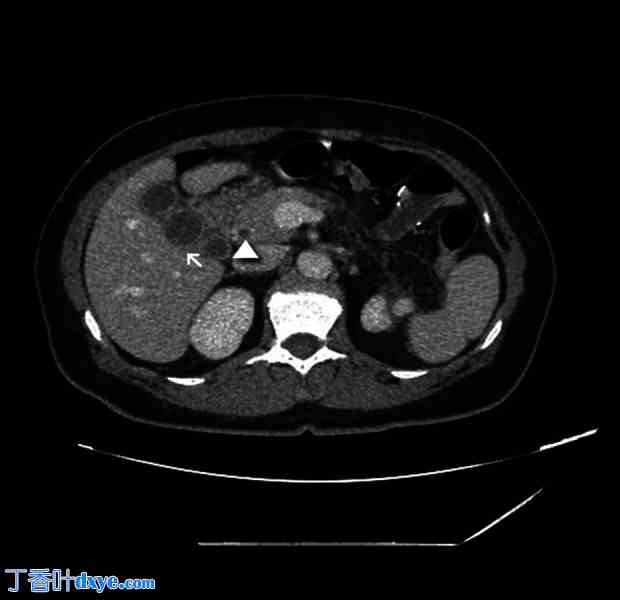

一名 42 岁女性因急性胰腺炎入院。她既往病史包括小肠切除术、子宫切除术及附件切除术、肠系膜淋巴结切除术、阑尾切除术和因神经内分泌肿瘤 (NET) 而进行的网膜切除术。她还接受过生长抑素治疗,并因复发性肾结石放置了输尿管支架。她有复发性腹痛病史,在入住我院之前,3 个月前因急性胆源性胰腺炎转入另一家医院。临床检查:右腹部压痛,无其他腹部体征。血液检查显示白细胞 (WBC) 计数 12.65×103/uL,C 反应蛋白 (CRP) 0.57 mg/dl,脂肪酶 4230 U/l。急诊腹部CT扫描显示胆囊和胆道内有微结石,胆管壁增厚(图1)。考虑到胆道内可能存在CT未显示的胆结石,作者进行了T2加权磁共振胰胆管造影(MRCP),结果显示胆囊胆总管结石(图2)。然而,只有3D冠状位重建图像才怀疑胆囊异常(图3)。

图1.

术前检查。腹部CT扫描显示胆囊壁增厚(箭头所示),胆总管扩张(三角形所示)。此外,胆囊的扭曲外观模拟了两个不同腔室的存在。